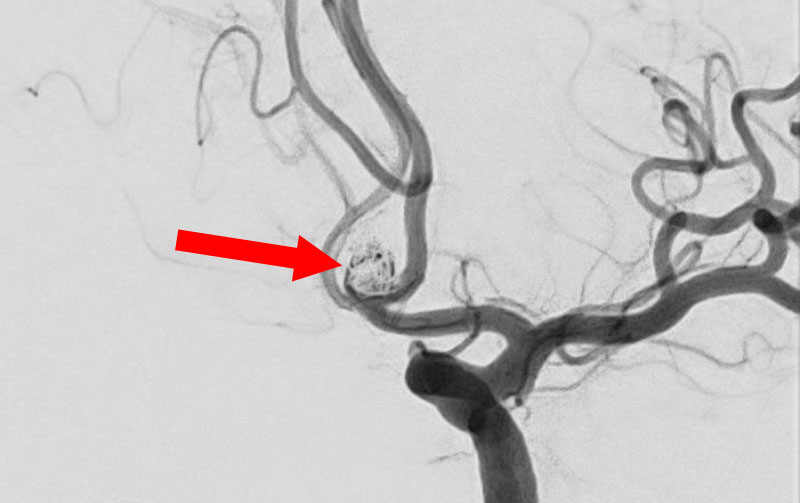

'25年11月

左内頚動脈脳動脈瘤

60代

大阪府の病院

No.1595 手術前

No.1595 手術中

No.1595 手術後